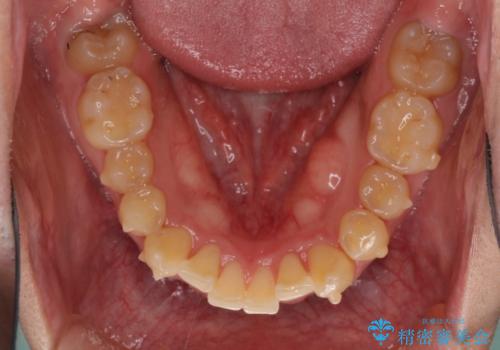

上顎のみの抜歯矯正をインビザラインで行う場合、奥歯の前方移動がインビザラインでは苦手のため、奥歯の咬み合わせが不十分となることがあります。

今回の治療では終了時に奥歯は接触しているものの、接触の程度は物足りないものがある状態でした。今後保定期間に少しずつ奥歯の咬合を改善させていくことになります。